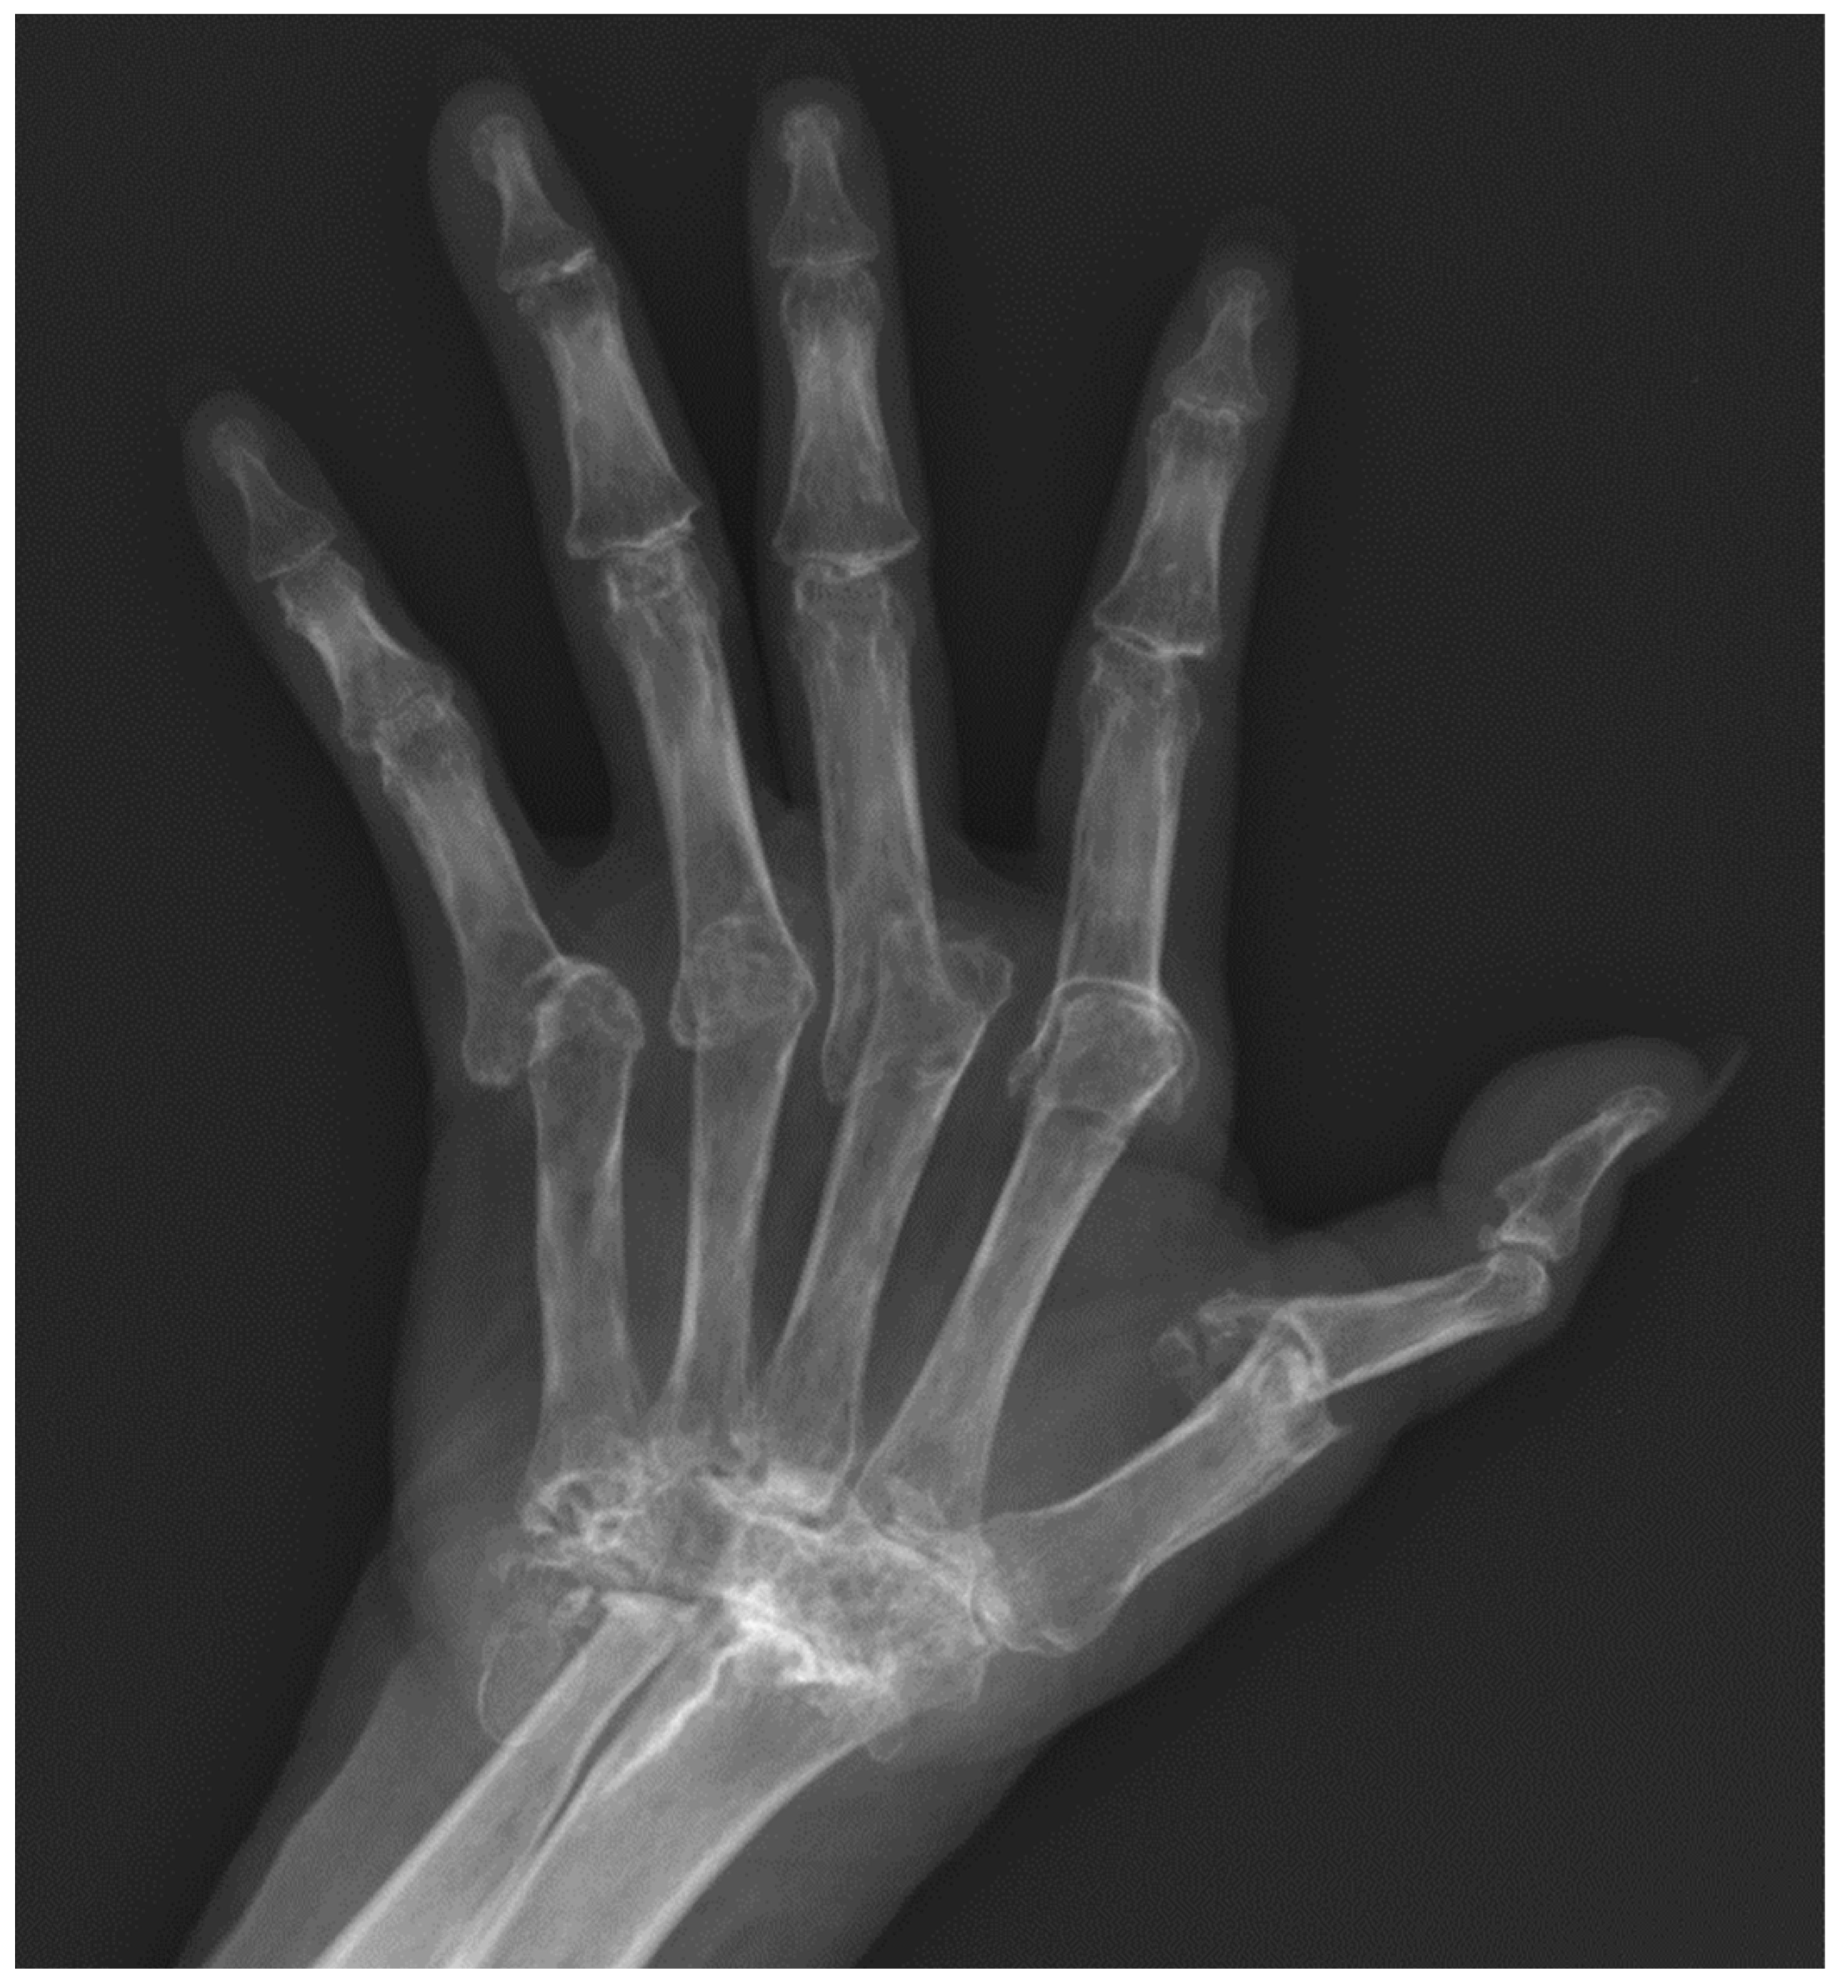

5. Psoriatic Arthritis (PsA)